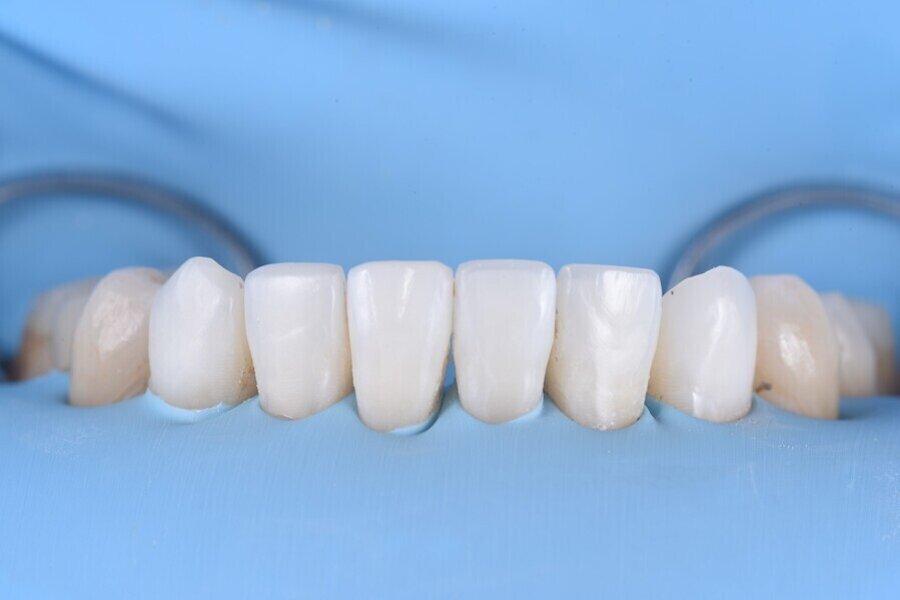

Obr. 4a–f: Návrh laterálních dostaveb v programu exocad.